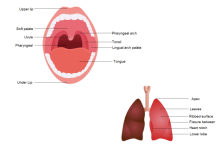

illustrazione scientifica - anatomia umana